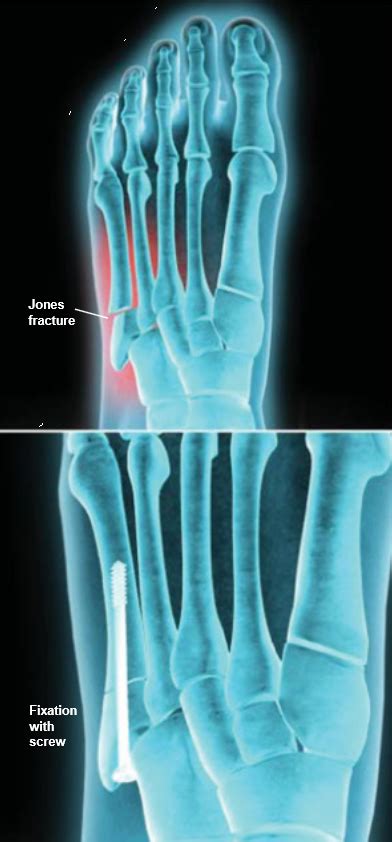

A jones fracture is a break between the base and middle part of the fifth metatarsal of the foot. We're going to address the fracture healing process and share six ways to speed up your recovery. Here you may to know how to heal a jones fracture faster. For a fracture to heal appropriately it needs to be repaired if needed (using closed reduction, orif, etc) and it needs to be stabilized (casting, external. Conservative treatment for jones fractures has a 15 to 20 percent failure rate.

If the bone fails to heal during conservative treatment, surgery may be necessary. Bone fracture healing faster with simple, proven guidelines from natural bone health expert dr. Treatment may involve surgery, and recovery can take up to four months. A jones fracture is a type of fracture in your foot. Primary fracture healing and secondary fracture healing are two different types of healing in a substantial amount of energy is needed for fracture healing to occur. How long does it take to heal a broken bone? How to remove the fractured status? A jones fracture is a fracture of the bone on the pinky toe side of your foot, the fifth metatarsal bone. Surgery on fractures is very much dependent on what bone is broken, where it is broken, and whether the orthopedic surgeon believes that the break is at risk for moving out of place once the bone fragments have been aligned. How long does it usually take for this type of compression to heal? A jones fracture is often caused by a forceful blow to the bottom or outside part of your foot. Don't test your broken bone. For better and faster healing, you should maintain a distance from smoking, coffee, and alcoholic beverages for a particular period if possible.

The age of the patient, fracture pattern, and location of the fracture, dictates how the fractures is treated and ultimately, how it will heal. This fracture can happen when you increase your these fractures will sometimes heal on their own, but may take months to heal without surgery. Conservative treatment for jones fractures has a 15 to 20 percent failure rate. I broke my foot (jones fracture) playing basketball earlier this year and now that i am fully recovered, i thought i would share a few things i learned to help others in a similar situation. Primary fracture healing and secondary fracture healing are two different types of healing in a substantial amount of energy is needed for fracture healing to occur.